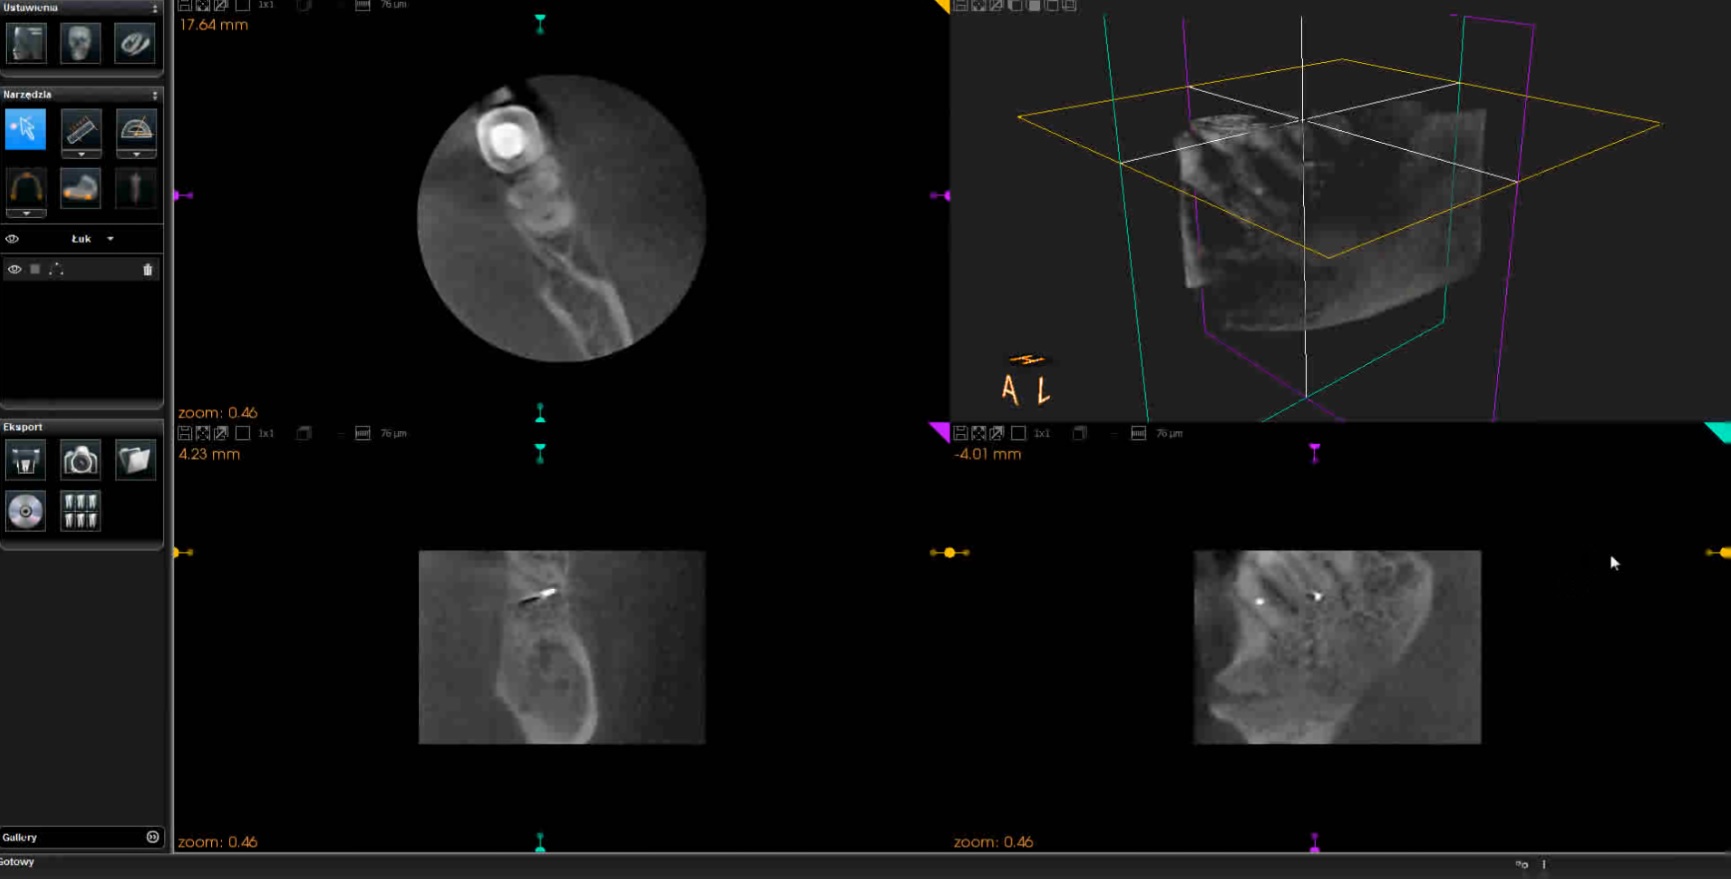

1

Film 1. Badanie CBCT potwierdzające lokalizację złamanych fragmentów narzędzi oraz perforację korzeni zębów w płaszczyźnie horyzontalnej. W filmie kursorem wskazywane są kolejne miejsca preparacji przestrzeni dla implantów ortodontycznych. Zmieniający się obraz przekroju horyzontalnego widoczny jest w lewej, górnej części ekranu.